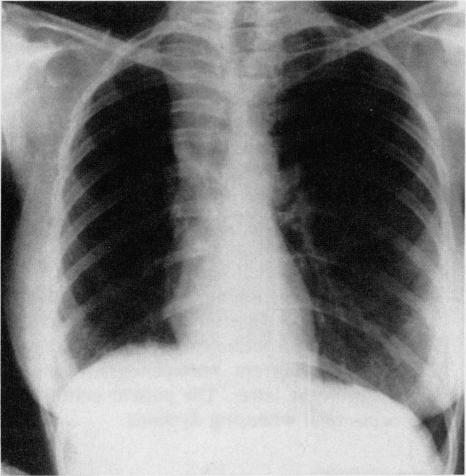

A case is presented of a 28-year-old woman with right upper lobe atelectasis secondary to sarcoid adenopathy. As most chest surgeons and physicians would currently remove the offending lymph nodes for lung reexpansion and more definitive diagnosis, the case is considered primarily for its historical interest.

本文报告一例28岁女性患者,因结节病性淋巴结病继发右上叶肺不张。由于目前大多数胸外科医生和内科医生会切除引起问题的淋巴结以实现肺复张并进行更明确的诊断,该病例主要因其历史意义而受到关注。